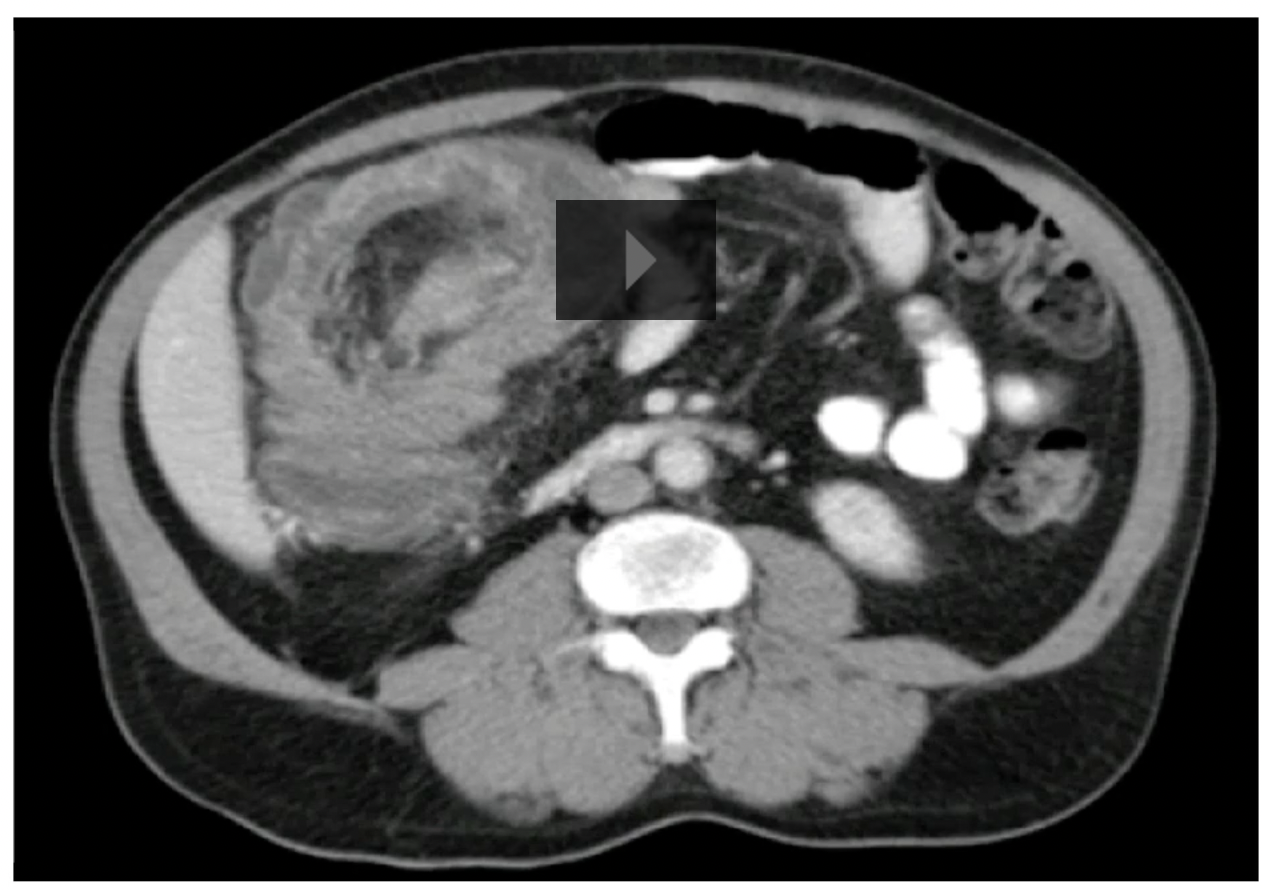

8

Q

A

Cecal volvulus

How well did you know this?